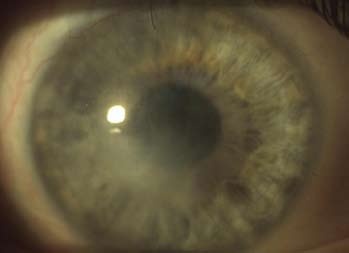

1. den po operaci (obr. 3) – na přání pacienta bylo svoláno psychologické konzilium.